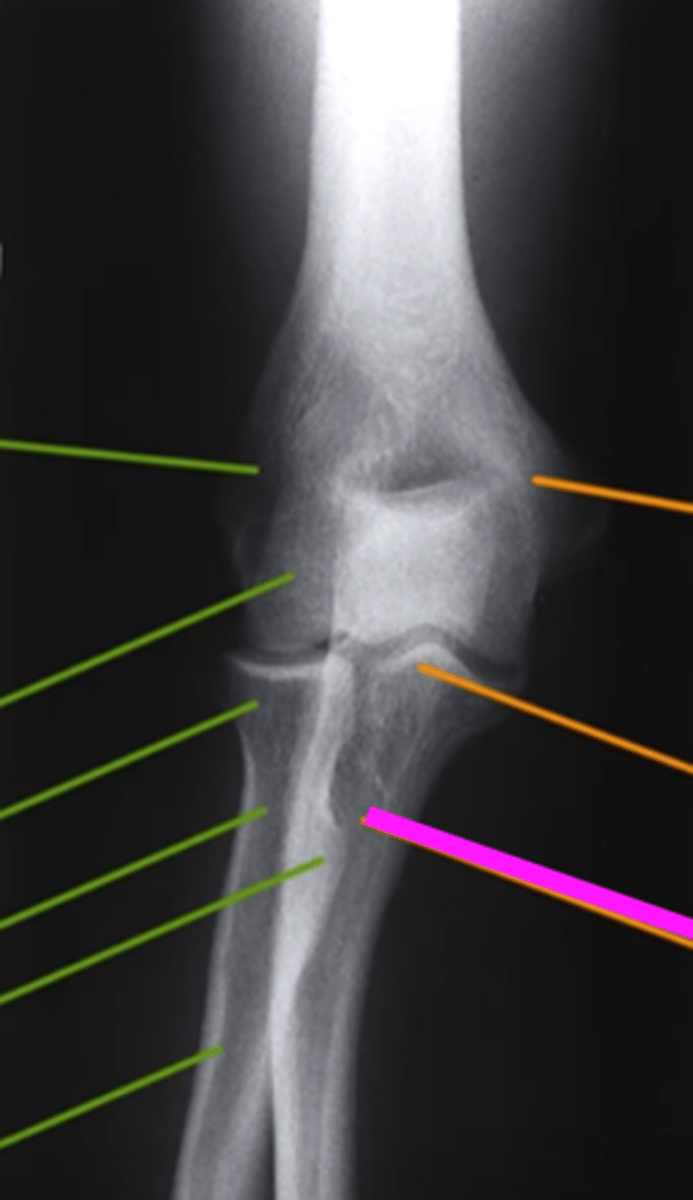

AP forearm

what view is this?

olecranon process

what does this pink line point to?

trochlea

capitulum

humeroradial joint

proximal radioulnar joint

radial tuberosity

radial styloid

distal radioulnar joint

scaphoid

lunate